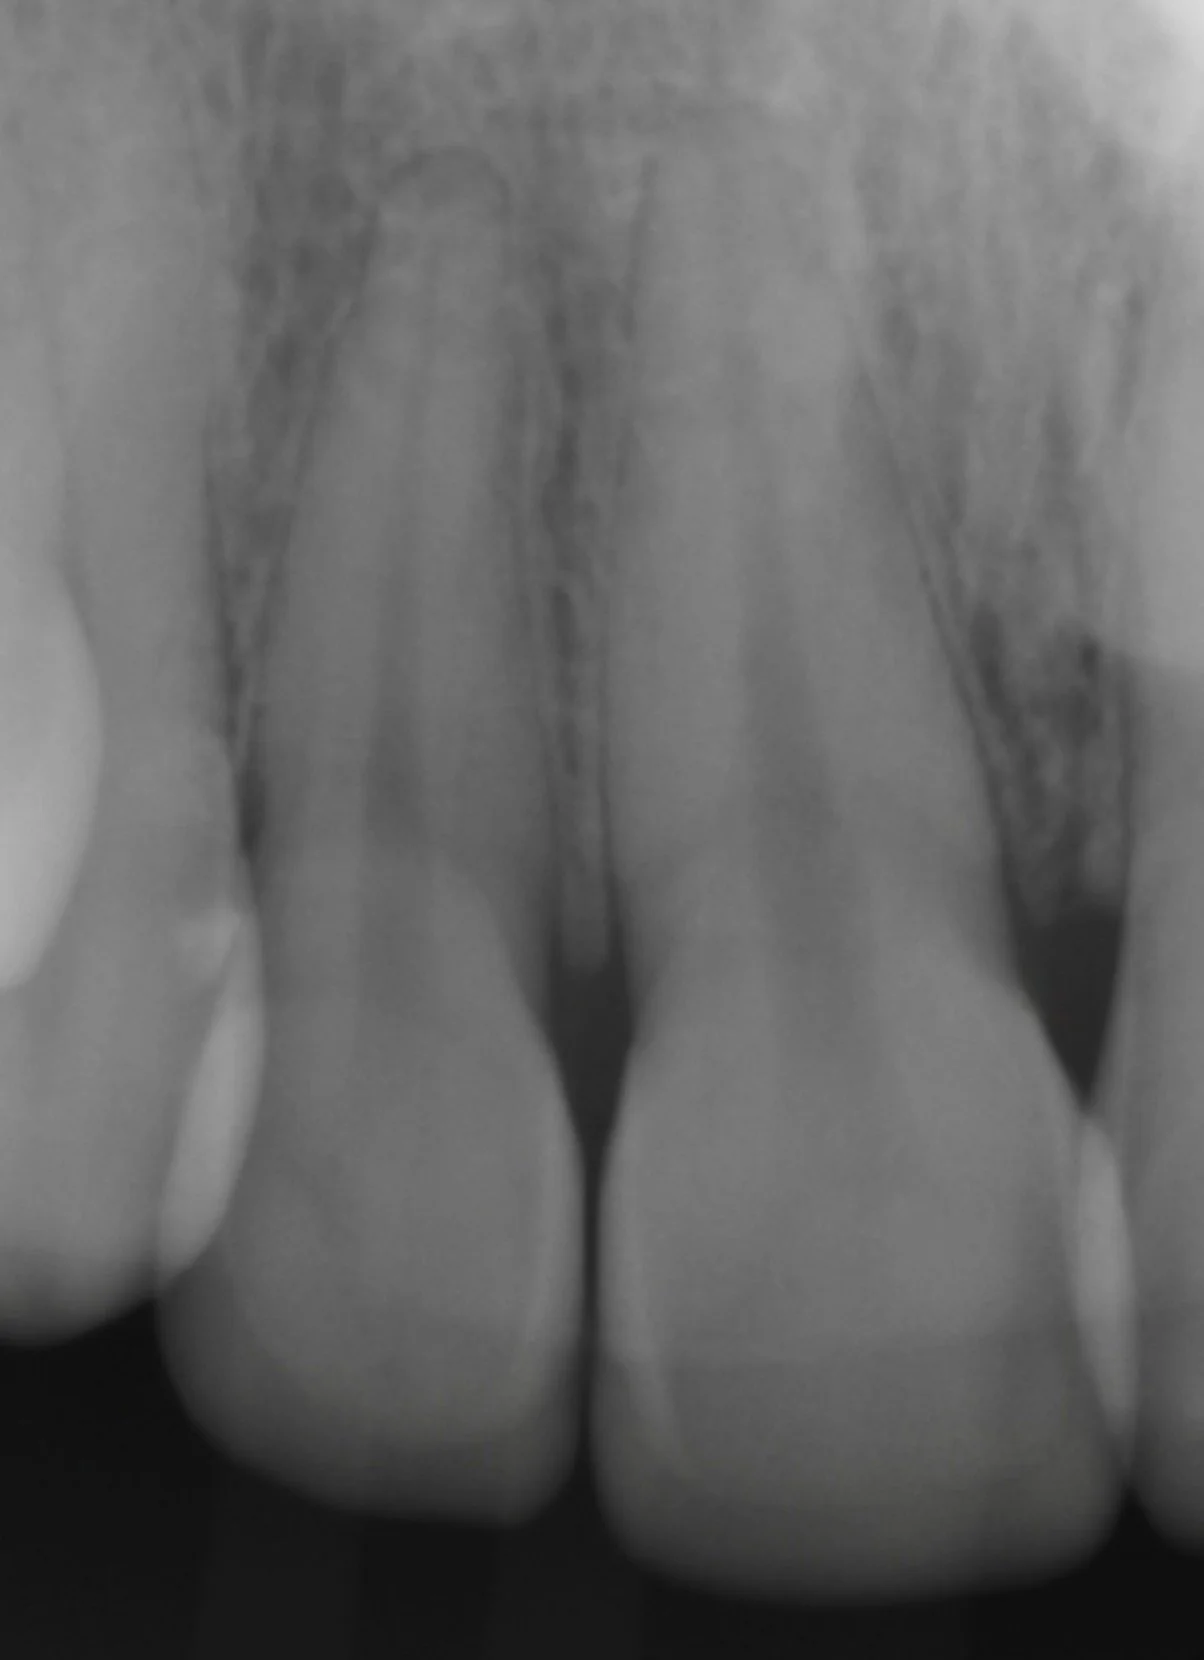

4 Minimal Prep Veneers in Shade 0.5M1

Dr. Heldt, 2025. Newport Beach, California.

Because the patient is not interested in orthodontics, we were able to have the teeth appear straightened with 4 veneers. This is not the doctor’s recommendation by the way. 4 Layered eMax Veneers (#7-10) in Shade 0.5M1. Diagnostic waxup with patient-approved temporaries for shape and shade. Low translucency. No staining.